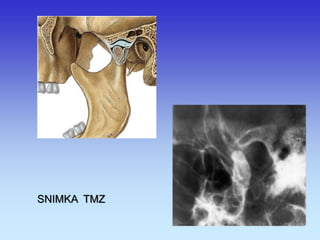

TEMPOROMANDIBULARNI ZGLOBOVI

SNIMKA TMZ